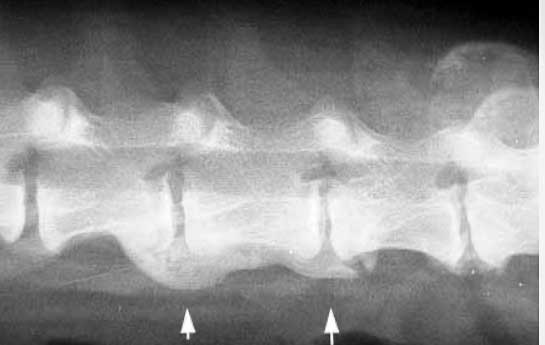

The arrows point to arthritis of the spine (called spondylosis) of the lumbar vertebrae